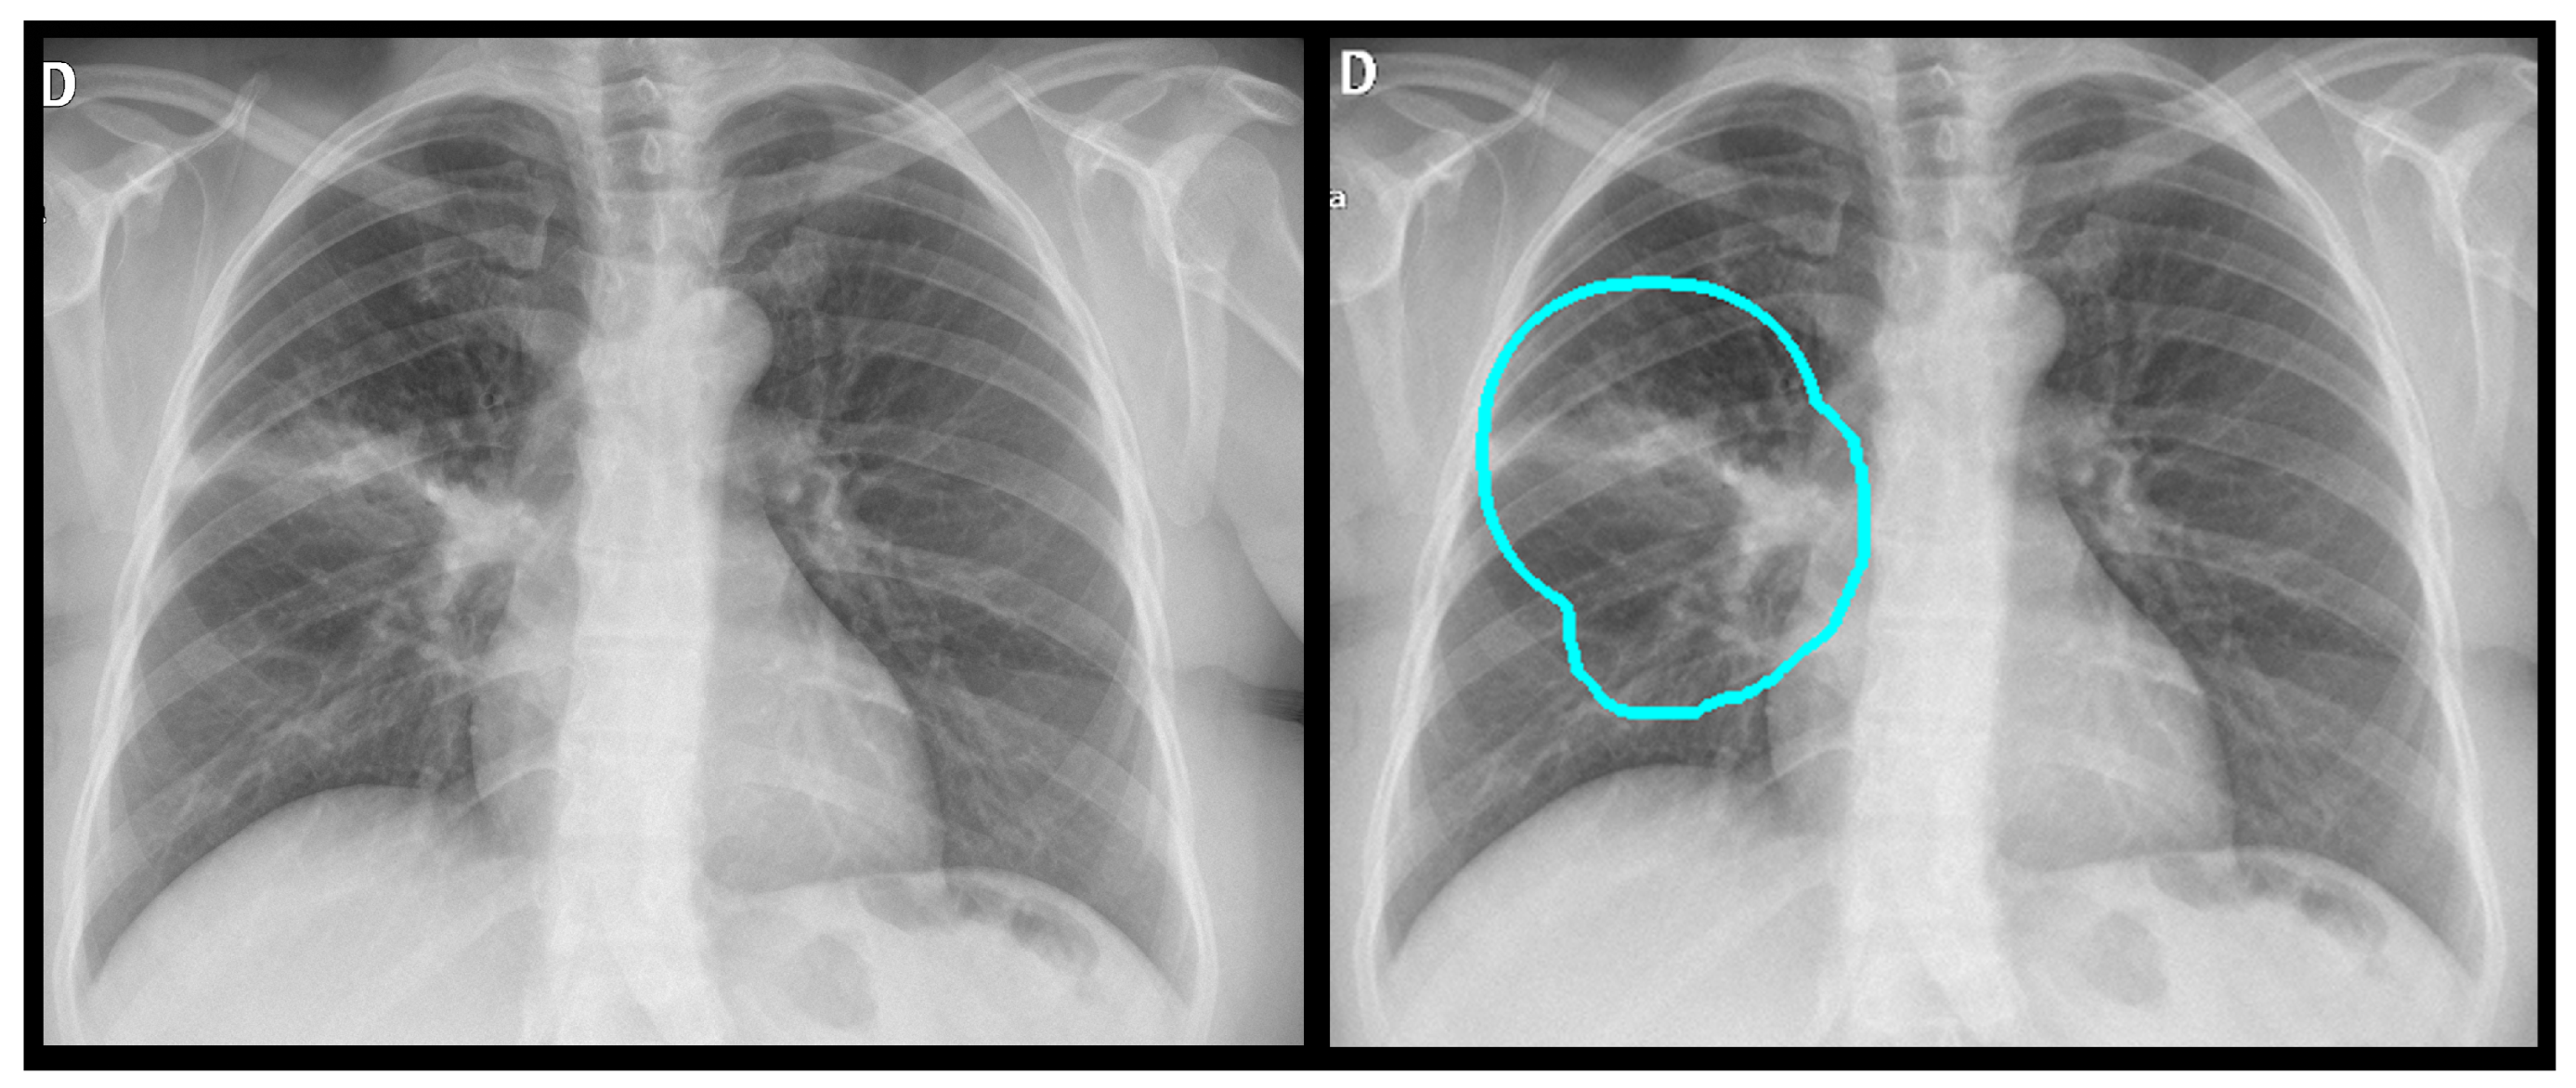

Before training, radiologists reviewed and verified the images, applying annotations using a proprietary software application (Figure 1). The dataset exhibited a significant class imbalance, reflecting the real-world prevalence of the pathology. For training binary classifiers, studies with definitive labels (1.0 for present, 0.0 for absent) were used. In contrast, studies with missing labels for a specific finding were excluded from the loss calculation for that task. Table 2 shows the distribution for a selection of key labels. The list of pathologies was selected based on the availability of labeled data, balanced with clinical importance for the ED. The ‘normal’ and ‘abnormal’ pools included cases with pathologies beyond the specifically targeted list; these were categorized under the general “yesfinding” class.

Figure 1. All labeled images were proofed by a radiologist who manually drew a region of interest around the pathology and assigned a finding, as shown here for an alveolar opacity circled by the dashed line.